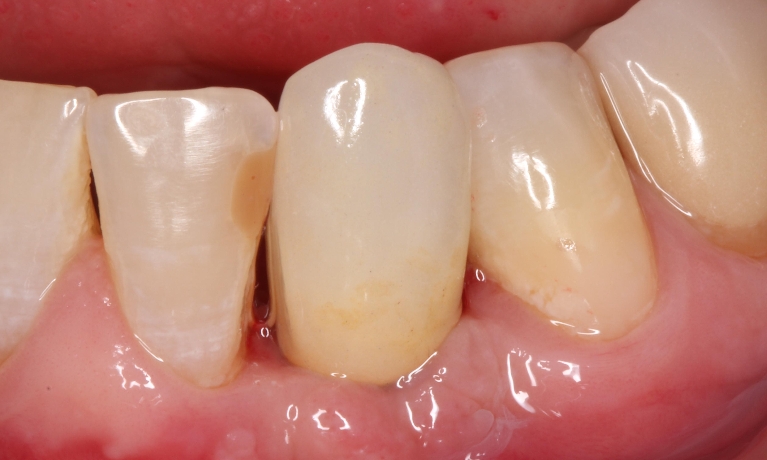

Stomatologiyanın təməl vəzifələrindən biri, itirilmiş dişlərin funksiya və estetik olaraq təbiiyə ən yaxın şəkildə bərpa edə bilməkdir. Dişsizliyin estetik və funksional olaraq yüksək səviyyədə reabilitasiyası, pasiyentlərin çeynəmə, danışma və gülmə kimi funksiyalarını qüsursuz icra edə bilməsi baxımından çox önəmlidir. Diş implantları xüsusi texnologiya hazırlanaraq, itirilmiş dişin bərpası üçün tətbiq edilən süni diş kökləridir. Bu metod təbiiyə ən yaxın bərpanı vəd edən müalicə metodu kimi uzun illərdən bəri beynəlxalq miqyasda geniş tətbiq olunur. İmplantasiya, bu işin peşəkarı yüksək ixtisaslı mütəxəssis tərəfindən qısa bir müddət davam edən prosedur vasitəsilə ağrısız, qısa müddətə və həyati funksiyaların məhdudlaşmaması şərti ilə həyata keçirilən müalicə üsuludur.

Dental implantlar əsasən titandan hazırlanır. Bu materialdan hazırlanmasının ən başlıca səbəbləri, bu metalın orqanizm tərəfindən rədd edilməməsi, heç bir allergik reaksiyaya səbəb olmaması və bu təyinat üçün yetərli möhkəmliyinin olmasıdır. Diş implantları vasitəsilə, tək diş əksikliyindən, çoxsaylı diş əksikliyi və tam dişsizlik halları funksional və estetik bərpa edilə bilir. İmplantın üzərinə hazırlanan diş konstruksiyaları müvafiq vəziyyətlərdə implantların tətbiqi ilə eyni gündə və ya müəyyən bir sağalma dövrünün keçməsindən sonra hazırlana bilir. İmplantların istismar müddəti, doğru planlama və icraat həyata keçirildiyində, eyni zamanda yetərli gigiyenik qulluq şəraitində bir neçə on illik bir periyodu əhatə edə bilir.